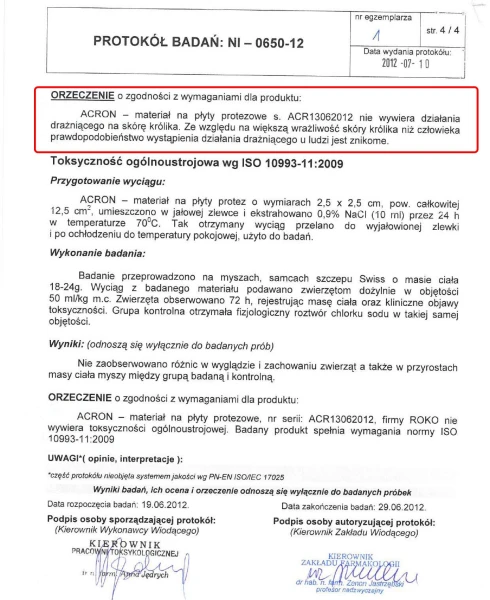

ACRON został gruntownie przebadany i przetestowany. Badania Narodowego Instytutu Leków wykazały, że nie zawiera substancji toksycznych i drażniących. Jest bezpieczny dla pacjentów i personelu medycznego.

DLA ALERGIKÓW

CERTYFIKACJA ISO